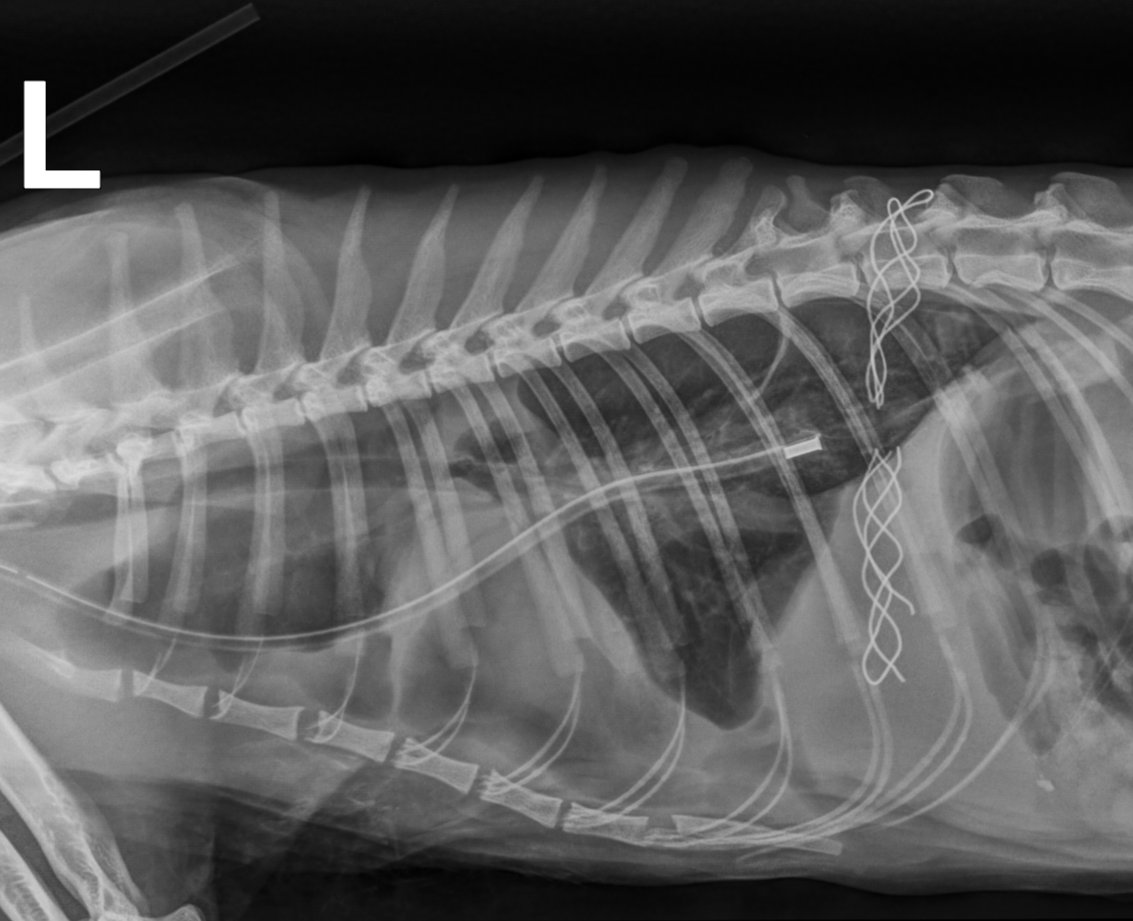

Als Maincoon-Kater Emil in die Praxis kam, dachten alle zuerst seine hochgradig erschwerte Atmung kam von einem Herzleiden mit Pleuraerguss (Flüssigkeit zwischen den Lungenlappen), welche unbehandelt zum Erstickungstod führt. Aber Emil „überraschte“ uns mit einem Pyothorax, d.h. Eiter im Brustkorb. Die Ursache hierfür blieb sein Geheimnis, sowohl kleine Verletzungen als auch Grannen können soetwas auslösen. Nach dem Legen einer Thoraxdrainage und mehrfach täglichem Spülen ging es Emil zum Glück stetig besser, sodass er nach ca. 10 Tagen wieder entlassen werden konnte. Im Nachgang muss er noch mehrere Wochen Antibiotika nehmen, damit es nicht zu einem Rezidiv kommt. Sein Herz ist zum Glück völlig ohne Anzeichen einer HCM (Hypertrophen Kardiomyopathie) und wird in noch lange bei seinen Abenteuern tatkräftig unterstützen.